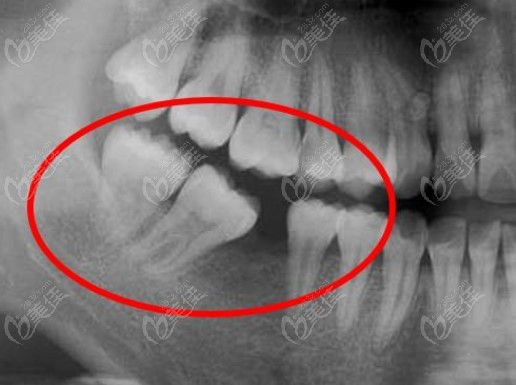

大牙片,大牙

牙片为医患沟通提供了准确的依据.

智齿,那个医生说先不拔,如果后面不疼就保留它,以便支撑旁边的大牙

大牙疼了好几天,一吃东西就疼,晚上不影响睡觉.吃药会好吗?有x光片.

大牙拔牙10年了还能再镶牙么如果可以是镶固定的好还是活动的好